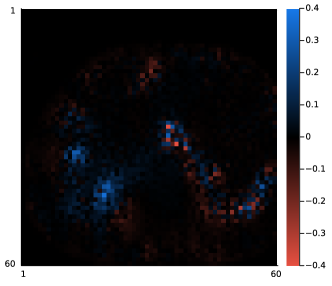

III-A3 Adjoint of projector

We generated a set of random numbers to verify that the backprojector is an exact adjoint of the forward projector. Specifically, we generated the system matrix of size (8×6×7)×(8×8×6)867886(8\times 6\times 7)\times(8\times 8\times 6) using random (nonnegative) attenuation maps and random (symmetric) PSF. Fig. 5 compares the transpose of the forward projector to the backprojector. As shown in Fig. 5 (d), the Frobenius norm error of our backprojector agrees well with the regular transpose within an accuracy of 106superscript10610^{-6} across 100 different realizations, as expected for 32-bit floating point calculations. A more comprehensive comparison is available in the code tests at https://github.com/JuliaImageRecon/SPECTrecon.jl.

Refer to caption

(a)

(b)

(c)

(d)

Figure 5: Accuracy of the backprojector. In subfigure (d), 𝑨superscript𝑨\bm{A}^{\prime} denotes regular transpose of 𝑨𝑨\bm{A}; 𝑨bsubscript𝑨𝑏\bm{A}_{b} denotes the backprojector.